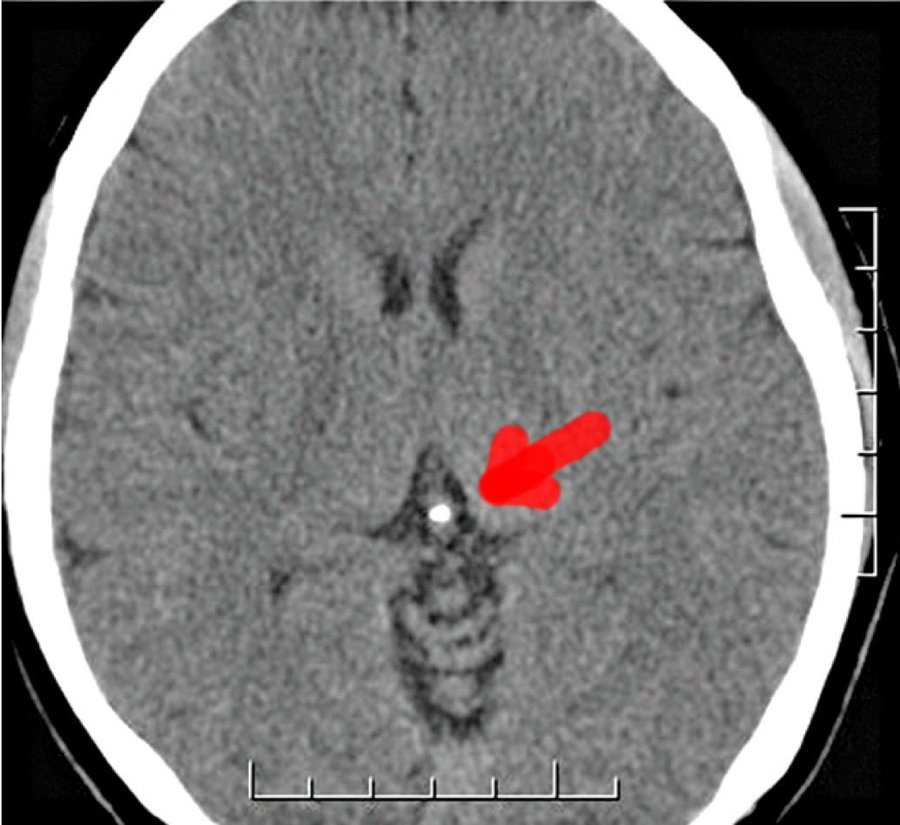

Over 75% of people over that age of 25 have a significantly calcified pineal gland.

In a 2001 study on fluoride distribution, pineal gland fluoride levels were measured in aged cadavers. Researchers found that:

“There was a positive correlation between pineal F[luoride] and pineal Ca[lcium] (r = 0.73, p<0.02) but no correlation between pineal F and bone F. By old age, the pineal gland has readily accumulated F and its F/Ca ratio is higher than bone.”[3]

They concluded that over time through regular fluorideexposure, “the pineal accumulates fluoride and that this accumulation may be implicated in the pathogenesis of pineal calcification. Given the essential role of the pineal gland and melatonin in regulating wake/sleep patterns, creativity, calmness and spiritual health, these findings have profound implications”

The pineal gland is an endocrine gland whose main function is the biosynthesis and secretion of melatonin, a hormone responsible for regulating circadian rhythms, e.g., the sleep/wake cycle. Due to its exceptionally high vascularization and its location outside the blood–brain barrier, the pineal gland may accumulate significant amounts of calcium and fluoride, making it the most fluoride-saturated organ of the human body. Both the calcification and accumulation of fluoride may result in melatonin deficiency.